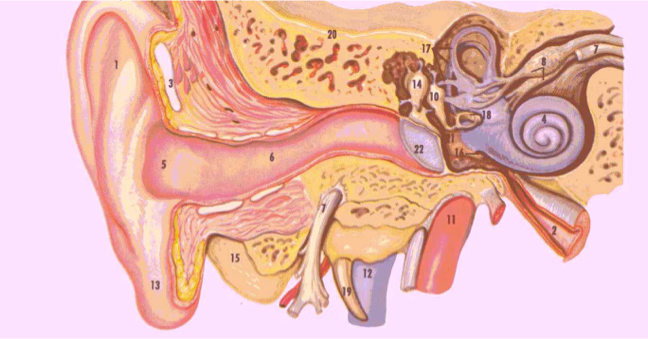

Intratemporal Complications

Labyrinthitis

Ossicular fixation or erosions

Labyrinthine fistula

Facial nerve paralysis

Mastoiditis / Mastoid abscess

Extracranial Complications

- Extension of infection to the neck

- Bezold abscess (extension of infection from mastoid to SCM)